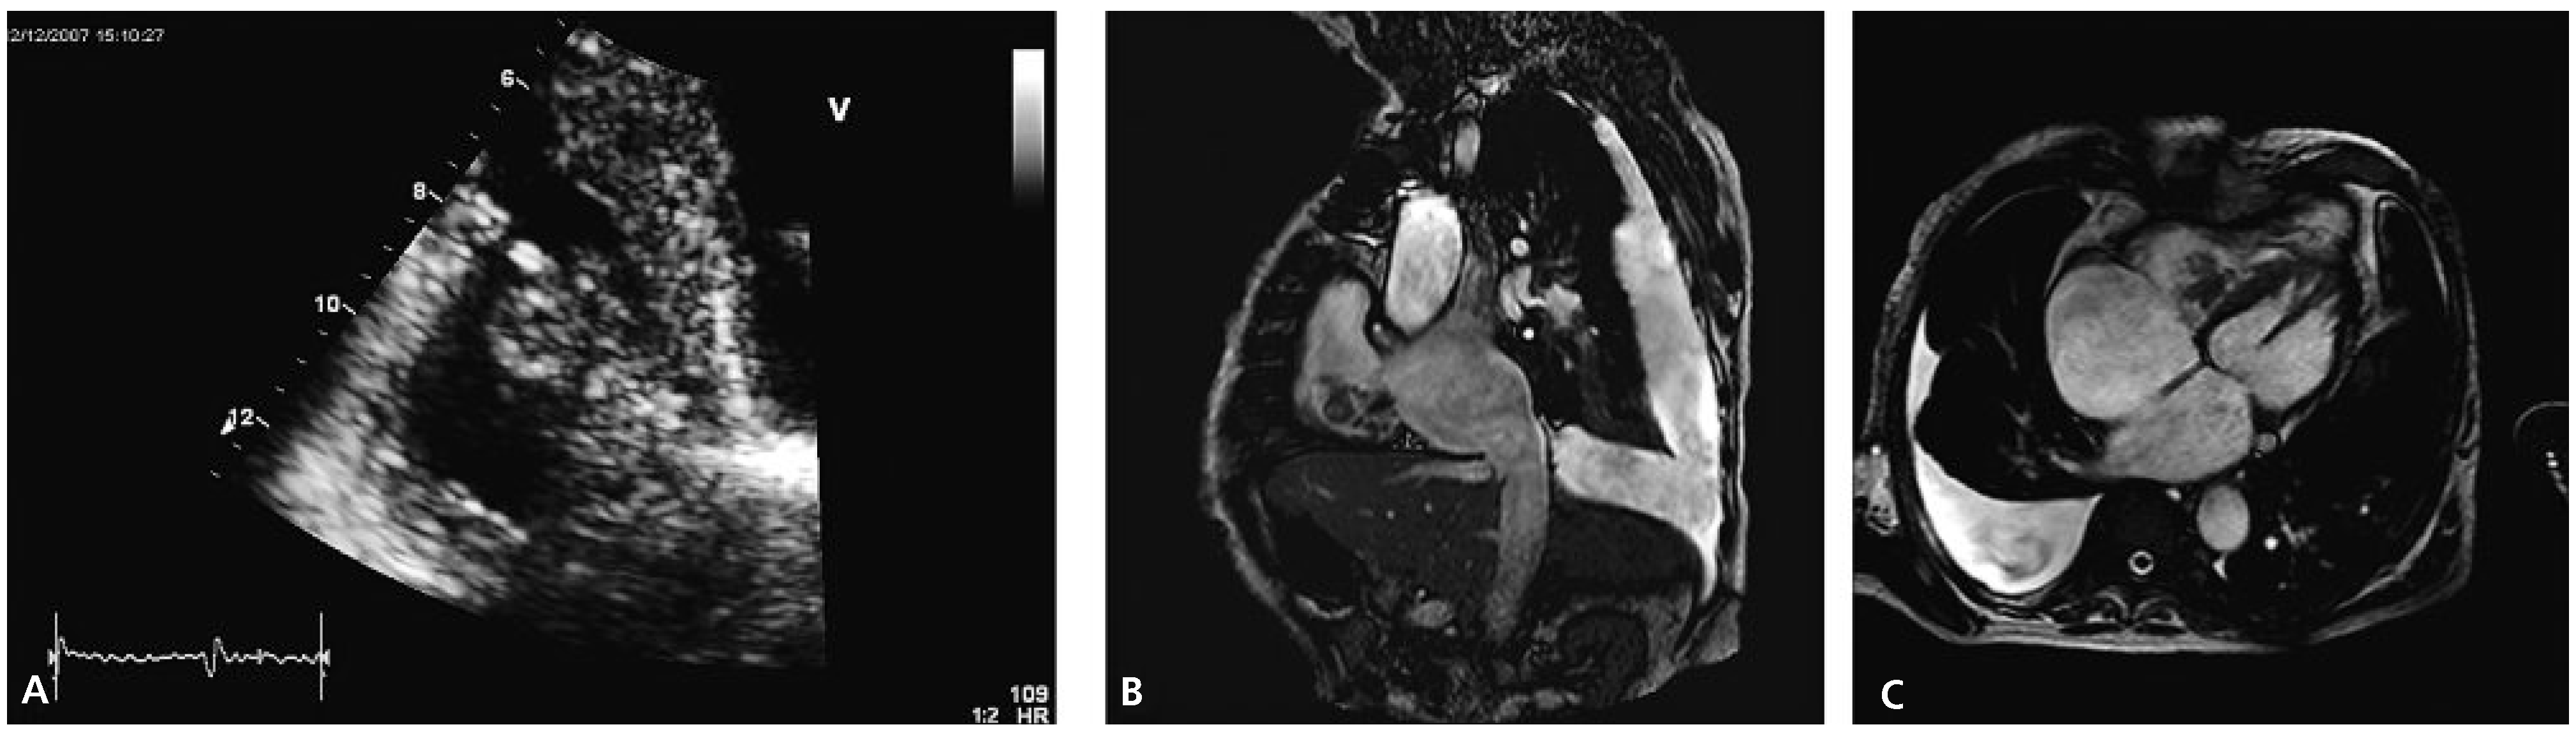

Transthoracic echocardiography revealed concentric left ventricular hypertrophy and a severely reduced global systolic left ventricular function (ejection fraction of 20–25%) due to inferior and posterior akinesia and substantial hypokinesia of the remaining wall segments. Both atria appeared dilated. The right ventricle was visually dilated with marked tricuspid annular dilation (50 mm) and functionally impaired (TAPSE 1.1 cm, TDI 10 cm/s). The aortic and mitral valves were remarkable for severe degenerative signs but besides a slight mitral regurgitation they were functionally normal. Attached to the septal leaflet of the tricuspid valve, an inhomogeneous structure partially prolapsing into the right atrium during systole was found (Figure 1A), associated with visually mild tricuspid valve regurgitation. The pressure gradient across the tricuspid valve was 65 mm Hg suggesting severely elevated systolic pulmonary arterial pressure. A CT scan of the chest confirmed pulmonary emboli in the right main pulmonary artery and in a segmental artery of the left upper lobe.

Cardiac MRI confirmed cardiac thrombus since there was no uptake of contrast agent and no signs suggestive of a tumour (Figure 1B,C). Antibiotics were stopped upon admission. Blood cultures remained negative and the CRP value remained low. Real-time PCR was positive for the V617F mutation of the JAK2-gene making the suspected diagnosis of polycythemia vera (PV) very likely. A bone marrow examination was refused by the patient. Phlebotomy (three times 500 mL) was performed and therapy with hydroxyurea (1000 mg/d) was started. Initially peripheral haematological values were checked daily and following discharge from the hospital they were checked weekly. The anticoagulation was changed to phenprocoumon in order to achieve less variable INR values. Additionally low-molecular weight heparins were applied until stable INR values between 2 and 3 were obtained. Due to the spontaneous intracranial bleeding eleven months earlier, therapy with acetylsalicylic acid was not added.

Figure 1. (A) Transthoracic echocardiogram showing a right ventricular mass (apical four chamber view). (B,C) Magnetic resonance images demonstrating a right ventricular thrombus.